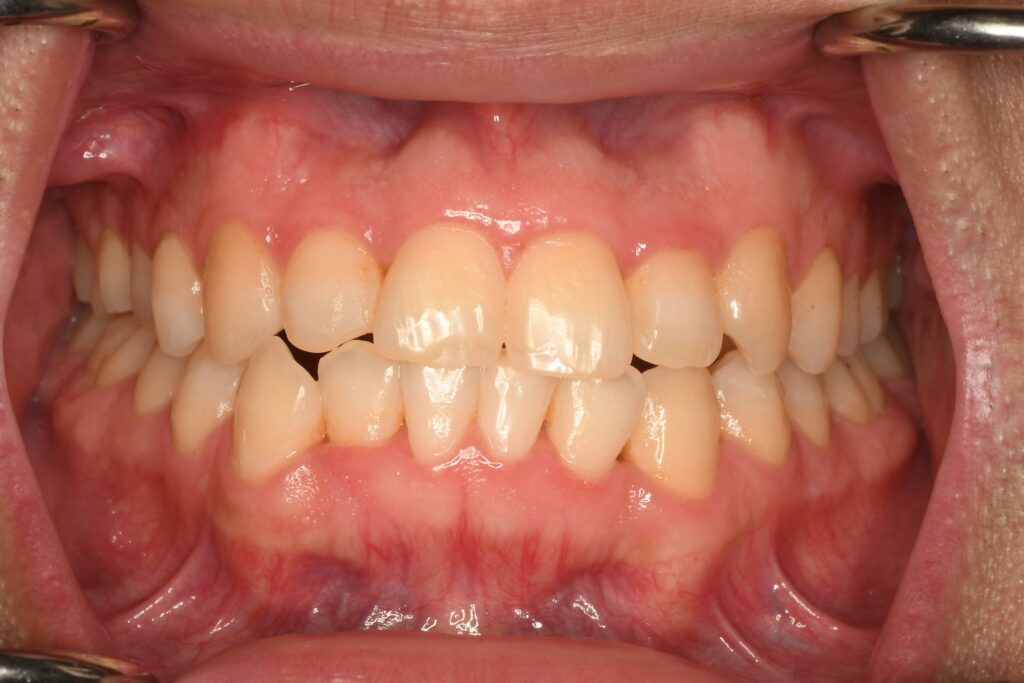

最初がこんな感じですから患者さんの満足してくれていますので、積極的な治療を終えて良くなった歯並びを保つためにリテーナーを装着してもらうことにしました。

「もっとこうしたい」がないわけではないのですが、患者さんが満足しているので積極的にはを動かすのは終了させて、この状態を保つことにしました。

インビザラインの矯正自体は1月に終わり、アライナーが届き、歯のアタッチメントの取り外しが終わりました。ここからはリテーナーでの生活になりますが、油断はせず今までと変わらず付けようと思います。アタッチメントは取れた瞬間、舌でなぞると開放された感を強く感じました。時間は追加アライナーなどで想定より1年多くかかってしまいましたが矯正してよかったです。